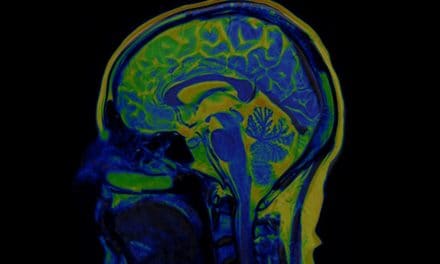

Sistemski eritemski lupus je autoimuna bolest koja zahvaća više organa, izaziva oticanje, bol, oštećenja tkiva, upale. Ova bolest kod koje organizam proizvodi protutijela na vlastite dijelove stanica praćena je nizom znakova i simptoma. Ovaj oblik lupusa može se pojaviti u svim dobnim skupinama, a najčešće pogađa žene u dobi od 15 do 45 godina. Organi koji mogu biti zahvaćeni ovom bolešću su koža, bubrezi, zglobovi, krv, centralni živčani sustav. Nije poznat točan uzrok nastanka bolesti, sklonost razvoju lupusa može biti potaknut nekim infekcijama, određenim lijekovima ili sunčevom svjetlošću, a važni čimbenici mogu biti genetska predispozicija i hormonski status.

Kod većine bolesnika javljaju se zglobno-mišićni simptomi, bolovi u zglobovima, a od kožnih promjena pojavljuje se crveni leptirasti osip na licu u području korijena nosa i na licu. Bolest oštećuje bubrege, krvni tlak može porasti do opasnih vrijednosti, a zbog oštećenja nervnih struktura bolest može dovesti do glavobolja, promjena ponašanja, napada epilepsije ili psihoza. U usnoj šupljini mogu se pojaviti ulceracije, afte, zglobovi su otečeni i bolni, javlja se ukočenost. Još postoji dosta simptoma koji prate ovu bolest, važno je s liječenjem i dijagnostikom započeti što ranije.

Teško je postaviti dijagnozu sistemskog eritemskog lupusa jer su simptomi i znakovi bolesti brojni i mogu biti slični s drugim autoimunim bolestima. Posebno je važno da se što ranije bolest dijagnosticira i započne s tretmanima koji mogu pomoći u kontroli simptoma, na žalost lijek za sistemski eritemski lupus još uvijek ne postoji, bolest često postaje kronična. U dijagnostici se provode laboratorijska testiranja krvi i urina, kao i dodatne pretrage. Kod ove bolesti mogu se dogoditi razdoblja bolesti s izraženim simptomima a nakon toga mogu doći razdoblja bez simptoma, koja mogu trajati godinama. Kod žena poslije menopauze rijetko se javljaju pogoršanja bolesnog stanja, stanje se može i dosta poboljšati. Liječenje zavisi o tome koji organi su bolešću zahvaćeni i o težini bolesti.